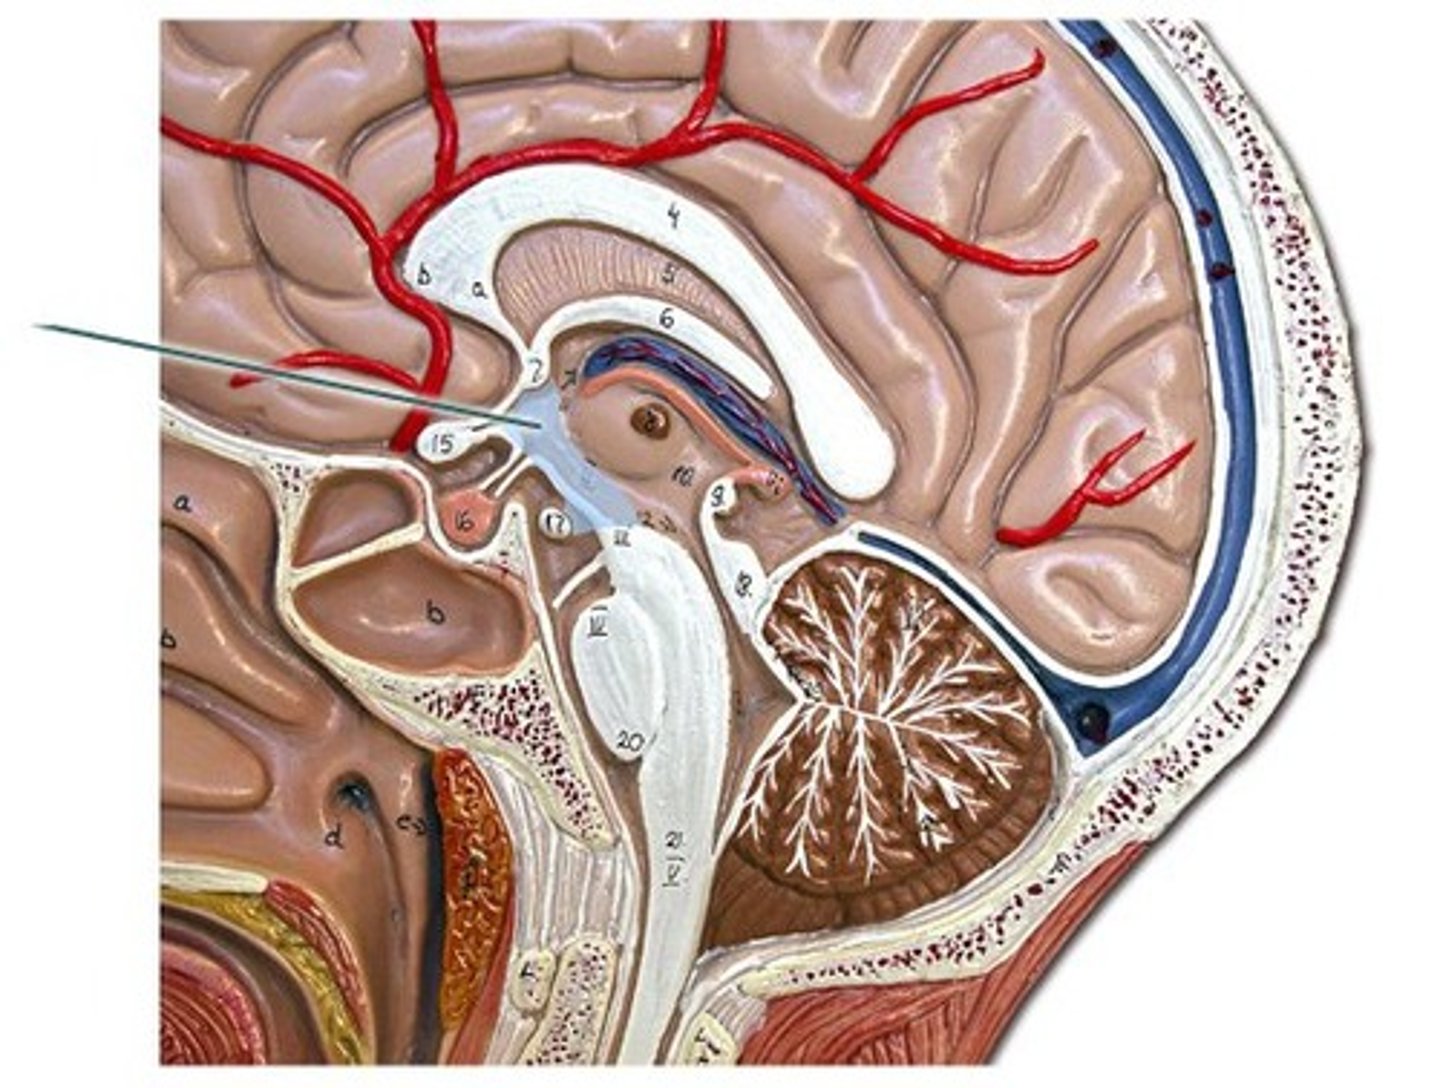

corpus callosum

septum pellucidum

optic chiasm

Interthalamic adhesion

Thalamus

Hypothalamus

Mammillary body

Pituitary gland

Pineal gland

choroid plexus

cerebral aqueduct

third ventricle

fourth ventricle

arachnoid villi

arachnoid mater of brain

dura mater of brain

pia mater of brain

falx cerebri

subarachnoid space of brain

pons

midbrain

medulla oblongata

arbor vitae